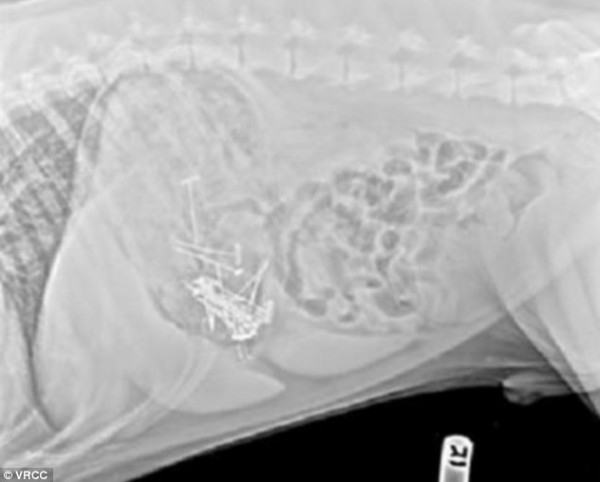

حيث قامت بالتهام البركان الصناعي وهو عبارة عن مشروع الفتاة بايتون "13 عام" الخاص بمادة العلوم والذي قامت بتصنيعه من قطع الحلوة وحبات شوكولاته M & M حيث قامت بلصق القطع ببعضها البعض بواسطة دبابيس صغيرة .

وتم نقل الكلبة إلى المشفى وتم إزالة أكثر من 50 دبوس معدني من عمدتها.